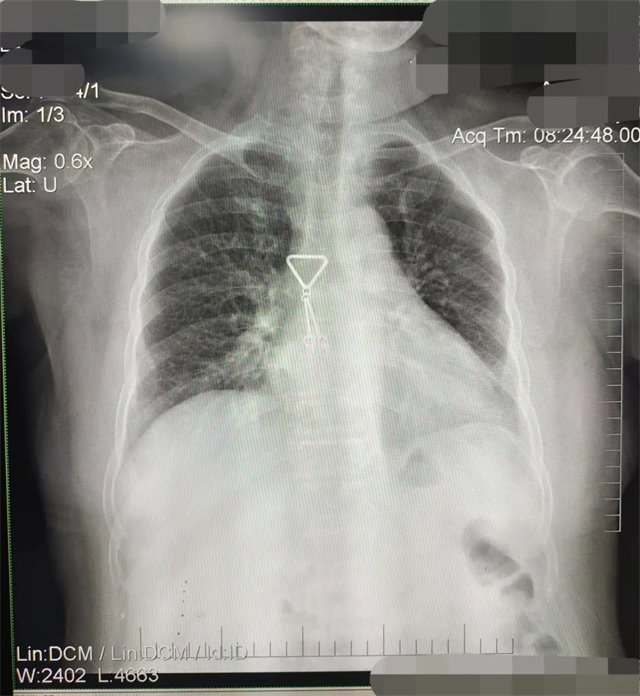

缺陷:兩肩胛骨未拉開肺野之外,吸氣不完全,且存在金屬飾品遮擋。

解決:去除金屬飾品及內(nèi)衣后重新按標(biāo)準(zhǔn)體位攝片即可。